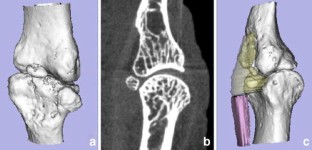

Flat-panel volume computed tomography (fpVCT) is a recent development in imaging. We discuss some of the musculoskeletal applications of a high-resolution flat-panel CT scanner. FpVCT has four main advantages over conventional multidetector computed tomography (MDCT): high-resolution imaging; volumetric coverage; dynamic imaging; omni-scanning. The overall effective dose of fpVCT is comparable to that of MDCT scanning. Although current fpVCT technology has higher spatial resolution, its contrast resolution is slightly lower than that of MDCT (5-10HU vs. 1-3HU respectively). We discuss the efficacy and potential utility of fpVCT in various applications related to musculoskeletal radiology and review some novel applications for pediatric bones, soft tissues, tumor perfusion, and imaging of tissue-engineered bone growth. We further discuss high-resolution CT and omni-scanning (combines fluoroscopic and tomographic imaging).